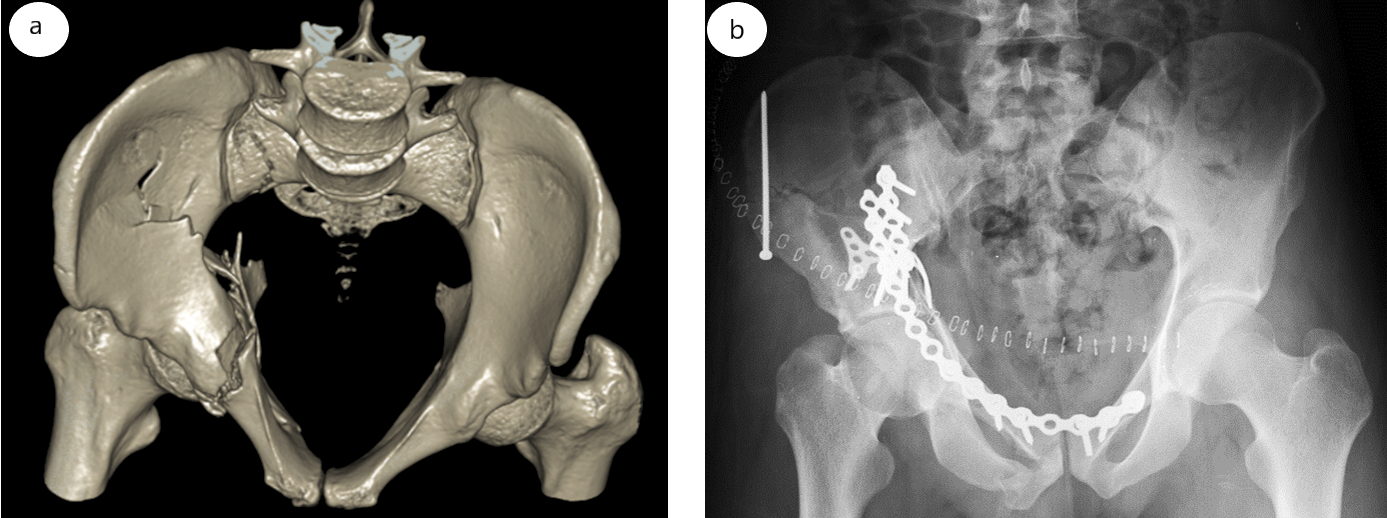

Пациент 29 лет пострадал в результате падения с высоты трех метров. Проведено оперативное вмешательство по поводу двухколонного перелома правой вертлужной впадины с медиальным смещением четырехугольной поверхности и головки бедра (рис. 4 а). В положении пациента на спине выполнили классический передний доступ к правой вертлужной впадине по Letournel. Произвели репозицию четырехугольной поверхности с помощью разработанного способа и двух щипцов Matta через медиальное и латеральное «окна» доступа. Фиксацию достигнутого положения выполнили T-образной подпружиненной пластиной с угловой стабильностью Synthes. Т-образную пластину предварительно изогнули под углом 100° в ее середине. Далее выполнили окончательный остеосинтез задней колонны тазовыми пластинами Matta (Stryker) и кортикальными винтами 3,5 мм (рис. 4 б).

Рис. 4. Двухколонный перелом правой вертлужной впадины (AO/OTA 62C1e): а — 3D-реконструкция КТ таза в проекции «вход»; b — послеоперационный рентгеновский снимок таза в прямой проекции